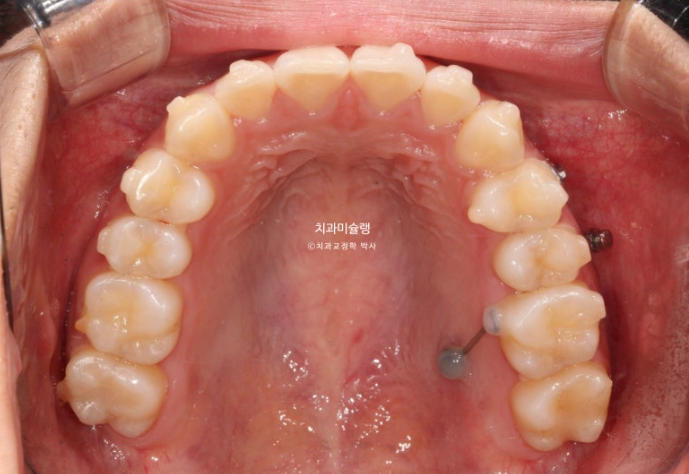

24.12

겨울방학때 입국하여 내원했을 당시 모습입니다.

어금니 후방이동을 위해 교정용 나사 미니스크류가 안팎으로 심겨져있습니다.

겨울 방학은 보통 짧습니다.

약 5개월치의 장치를 추가로 챙겨 출국 후 여름방학때 다시 내원한 모습입니다.